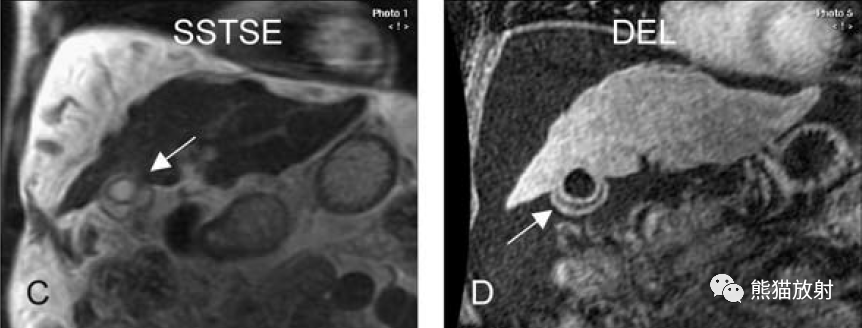

膽囊癌。A~D圖:上方層面,表現(xiàn)如上所述,形成腫物侵及肝臟。E、F圖:下方層面示膽囊壁不規(guī)則增厚,明顯不均質(zhì)強(qiáng)化。

膽囊壁增厚(并肝硬化、門脈高壓、腹水)。T2WI顯示膽囊壁因水腫而光滑均勻增厚,增強(qiáng)延遲期顯示強(qiáng)化的膽囊壁(內(nèi)外兩層:粘膜層和漿膜層),薄而清晰光滑。